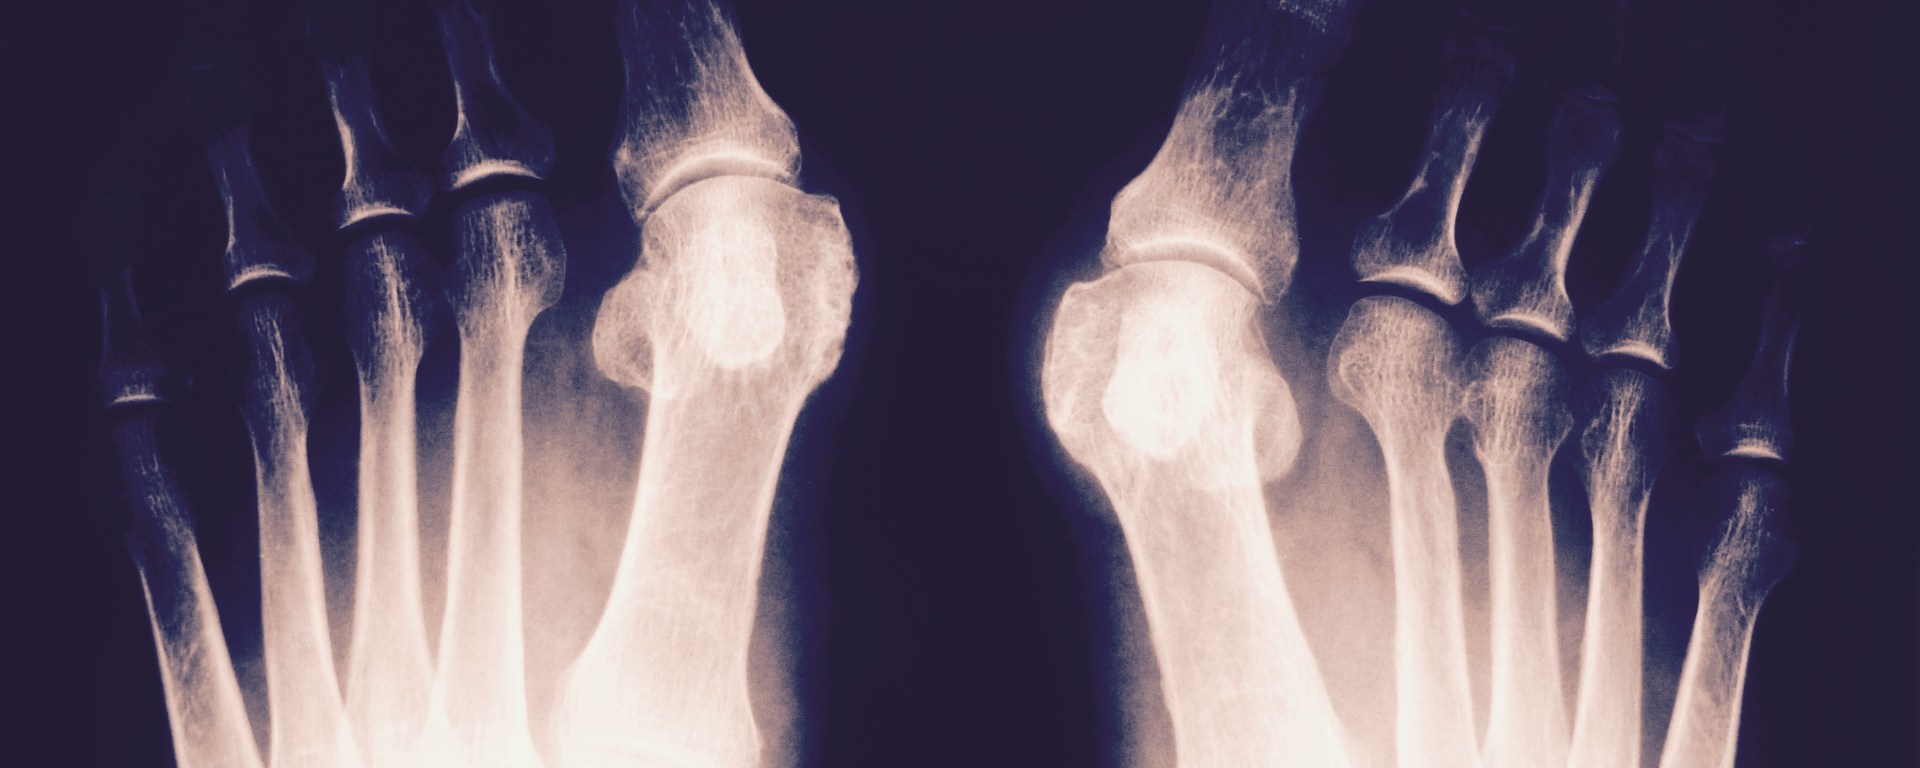

Some readers may have been wondering, what happened to all the fitness posts? Well, as of right now my running days are pretty much over, and I’m keeping things low-key for a reason. Those are not my feet in the x-ray image above, but mine very well could look like that if I don’t take it easy on my bunion.

Wearing high heels or pointed shoes for extended periods of time causes the big toe to squish inward, toward or even underneath the other toes. If not corrected, the toe will continue to grow out of alignment, and an extra piece of bone can start growing on the outside of the foot. As you can imagine, removing the extra bone surgically and re-setting the toe joints is incredibly painful, doesn’t always work, and puts the patient in a wheelchair for recovery. Let’s just say I do not want it to get to this point!

Luckily, mine is in the beginning stages, and though I may always have a bit of a nub on the side of my foot, I may not need surgery if I can slowly relax my foot muscles back into their correct positions.